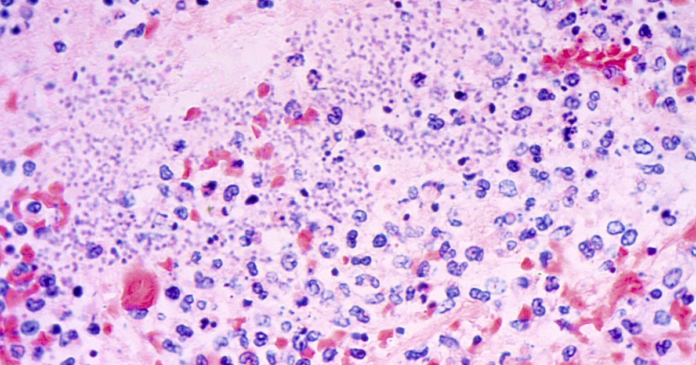

Plague is rare to humans, with on average about seven cases reported annually in the U.S., most of them in the western states, according to federal health of… [1961 chars]